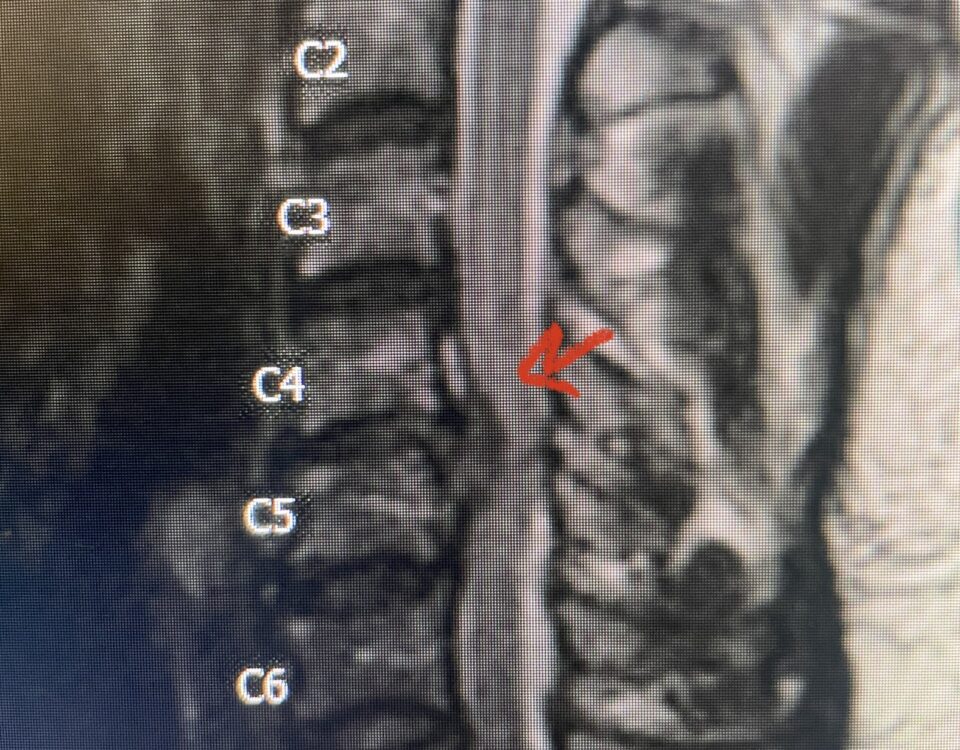

Here is a tough case: This is a 72 year-old male who presented with several months of progressive neck pain without symptoms of the arms or legs. […]